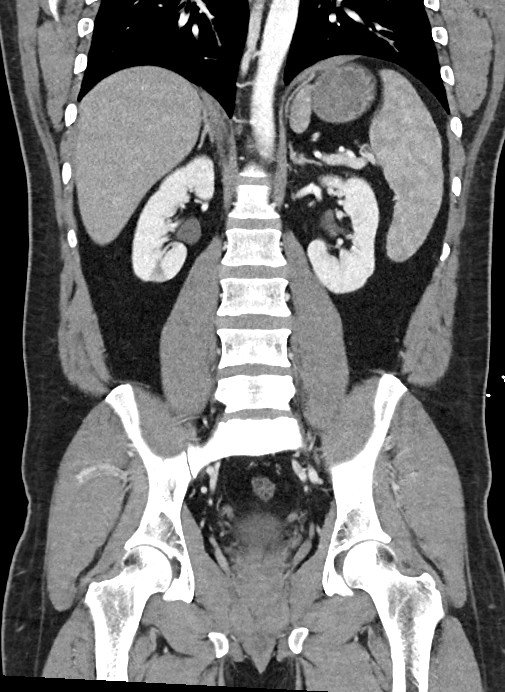

The Coronal View

This is also derived from a Latin word corona meaning “crown”. A coronal view follows the plane of the coronal suture of the skull which run across the top of the head, from ear to ear.

This view is best for evaluating long vertical structures like the aorta and IVC. And for checking symmetry across the body’s left and right sides like when evaluating presence of hydronephrosis / hydroureters.